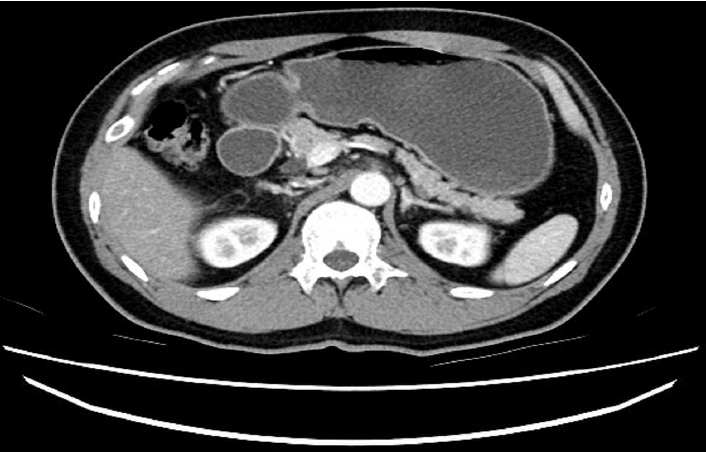

Figure 4.

Abdominal computed tomography scan showing annular pancreas encircling the descending part of the duodenum.

39세 남자 환자가 내원 1개월 전부터 발생한 상복부 불편감과 트림, 1주일 전부터 발생한 심한 구역과 구토로 인근 병원에 방문하여 입원 치료를 하였는데도 호전이 없어 전원되었다. 환자는 과거 특이 병력이 없었고 내원 몇 주 전에 검진 위 내시경상 특이 소견 없었다고 한다. 가족력 및 사회력에서 특이 사항은 없었다. 내원 당시 활력징후는 혈압 120/70 mmHg, 맥박98회/분, 호흡수 20회/분, 체온 36.6℃였다. 복부 진찰에서 장음은 감소되어 있었고 복부는 부드러웠으며 만져지는 종물이 없었고 압통 및 반발통도 없었다. 혈액 검사에서 백혈구 13,350/mm3 (중성구 75%), 혈색소 17.9 g/dL, 혈소판 529,000/mm3였다. 생화학 검사에서 혈액요소질소 74.1 mg/dL, 크레아티닌 4.24 mg/dL, 총 단백 6.4 g/dL, 알부민 4.1 g/dL, 총 빌리루빈 1.64 mg/dL, 직접형 빌리루빈 0.79 mg/dL, aspartate transaminase 20 IU/L, alanine transaminase 44 IU/L, alkaline phosphatase 141 IU/L, gamma-glutamyl transpeptidase 85 IU/L, C-반응성단백 4.84 mg/dL, Na 141 mEq/L, K 3.9 mEq/L, Cl 90 mEq/L였다. 타 병원에서 시행한 조영제 복부 컴퓨터단층촬영에서 위, 십이지장 구부가 확장되어 있었고(Fig. 1) 위 내시경에서 LA 분류 B의 역류성 식도염, 위체부에 담즙과 위 내용물이 가득 남아있는 소견(Fig. 2) 및 십이지장 두 번째 부분의 협착 소견이 보였다(Fig. 3). 환자에게 증상 완화를 위한 L-tube 삽입을 설명하고 시도하였으나 환자가 협조하지 않아 실패하였다. 입원 시 시행한 혈액 검사에서 크레아티닌 수치가 높아 전신성 급성 신손상 가능성이 있어 금식하면서 수액 치료를 시작하며 경과 관찰하였다. 외부에서 촬영한 조영제 복부 컴퓨터단층촬영에 대해 본원 영상의학과에 문의하였으며 고리 췌장에 의한 십이지장 폐색 가능성이 있음을 회신받았다(Fig. 4). 췌장 magnetic resonance imaging 및 magnetic resonance cholangiopancreatography (MRCP)를 검사하였고 같은 소견이었다(Fig. 5). 입원 4일째 복강경하위공장연결술을 시행하였고 이후 특별한 합병증 없어 퇴원하였다. 1년 후 환자는 증상의 재발 없이 외래에서 추적 관찰 중이다.